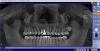

taurus1010 Опубликовано 20 сентября, 2012 Поделиться Опубликовано 20 сентября, 2012 Уважаемые хирурги!Хотел бы узнать ваше авторитетное мнение по моему случаю.1. Детская травма - выбили 11-ый зуб в 10-летнем возрасте.2. Через 15 лет почувствовал давление в области. Сфотографировал -- киста над 11,12. (См. снимок "2003 г").3. с 2003 по 2007 было произведено четыре резекции верхушек корней без подсадки костного материала. Четыре, т.к. были свищи, болевые ощущения, недомогание.4. После последней резекции с 2007-2008 года состояние стабилизировалось. Не беспокоило. (См. снимок "дек 2010_контрольный")5. В августе 2012 происходит продольный перелом 12 зуба (жесточайше кусанул замерзшую в камень изюмину в мороженом, блин...). Обломок лицевой части коронки уходит на 3 мм. под десну. (См. цветные фото)6.Предложено: а)удаление 12, 11 зубов, чистка кистозной зоны и одномоментная имплантация (+подсадка синт.костного материала от Альфа Био) с немедленным временным протезированием на временных абатментах с выведением коронок из прикуса и шинированием конструкции на период остеоинтеграции посредством объединения временных коронок между собой. б)Также есть предложение классическое: удаление 11,12-->аутокостная пластика с мембраной+ бабочка--> 3 месяца-->контроль-->имплантация+ бабочка--> 6 мес.--->контроль--> постоянное протезирование безметалловой керамикой. Вопрос:1.Какой план лечения по вашему мнению будет оптимальным с учетом эстетически важной зоны?(Классическая: аутокостная пластика+бабочка+отсроченная имплантация ч/з 3 мес.либо одномоментная имплантация + бабочка, либо одномоментная имплантация + временные коронки)2. Показана ли мне немедленная имплантация после удаления зубов с учетом истории болезни (хронический процесс)?3. Возможно ли при одномоментной имплантации провести кюретаж с высокой эффективностью, чтобы возможная инфекция не привела в отдаленной перспективе к потере имплантата?4. Сравнимы ли будут отдаленные результаты немедленной и классич.имплантации в моем случае?5. Бабочка. Испортит ли она мне междесневые сосочки? Есть противоположные мнения. Благодарю. Ссылка на комментарий